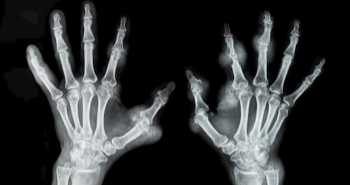

Сравнение эффективности ортезов при остеоартрозе большого пальца руки

Целью данного метаанализа было определение наиболее подходящего варианта ортеза для пациентов с остеоартрозом (ОА) большого пальца руки.